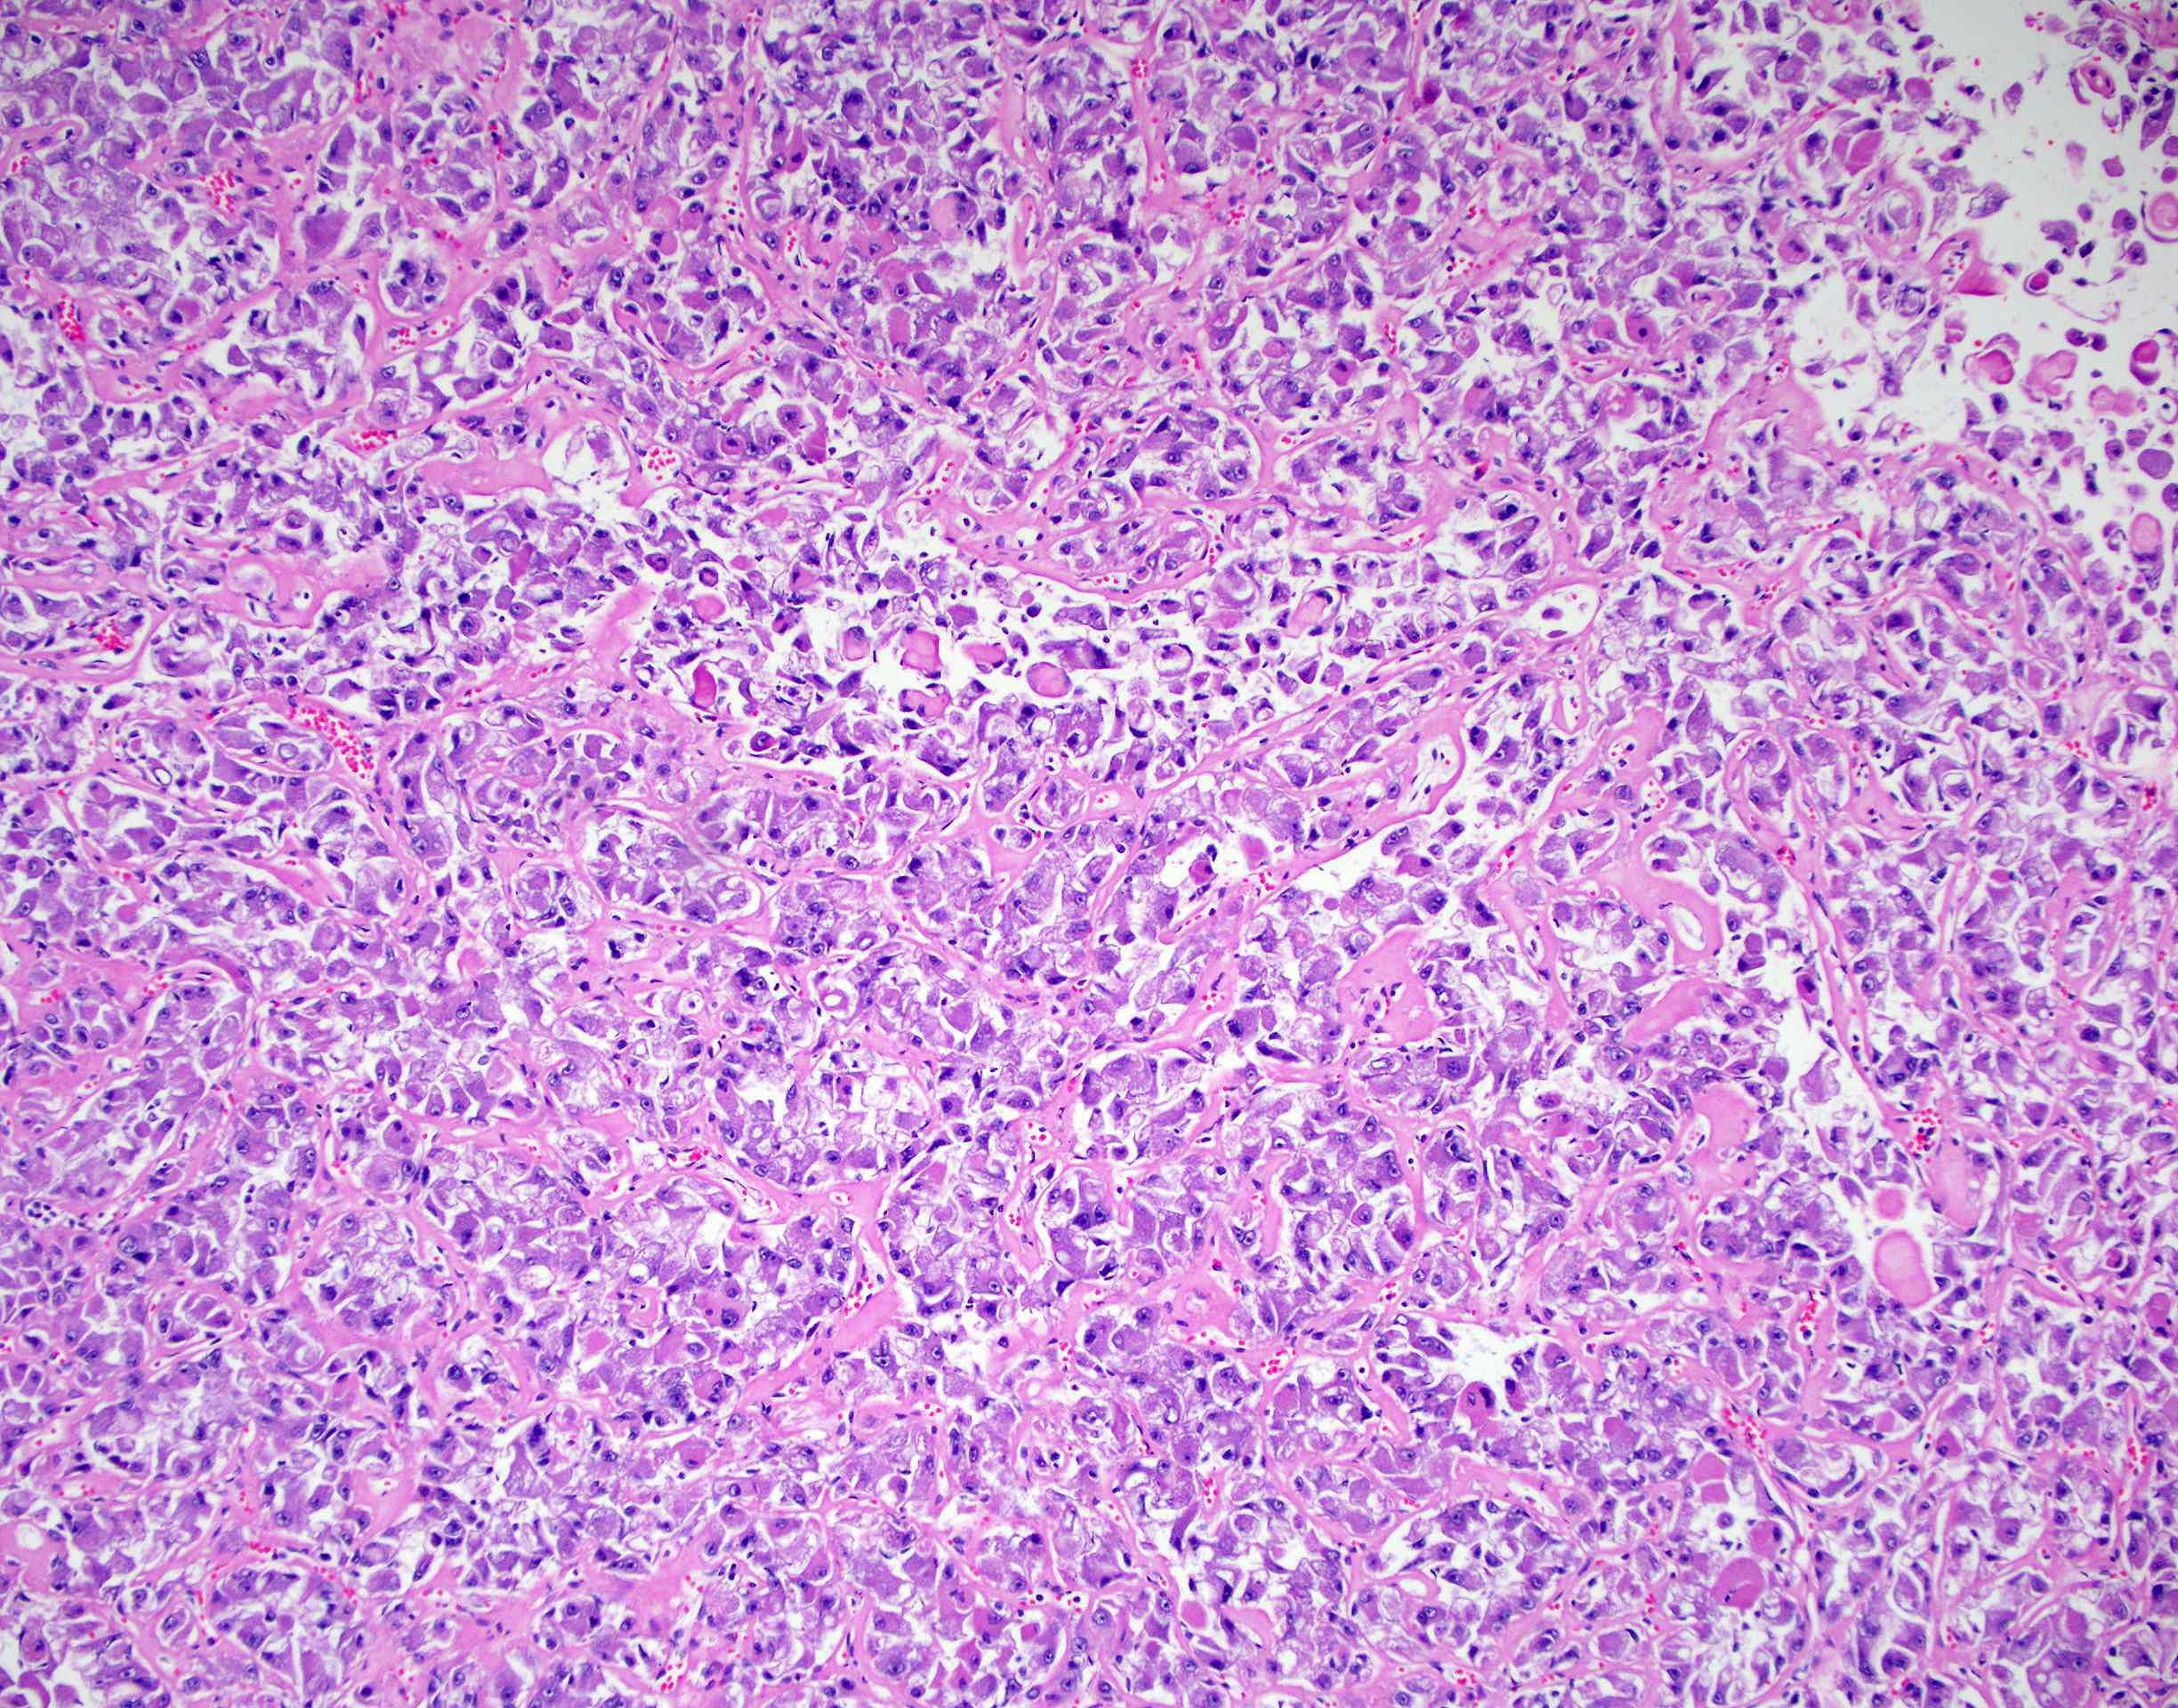

Renal tumor grading

Case ID: 419